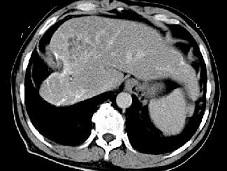

问题 女性,56岁,腹胀、双下肢浮肿、乏力、食欲不振,影像所见如下图,最佳的诊断是 ( )

选项 A.酒精性肝硬化并肝血管瘤 B.血吸虫肝硬化并肝癌 C.肝炎后肝硬化并肝癌 D.局限性脂肪肝 E.原发性肝癌

答案 B